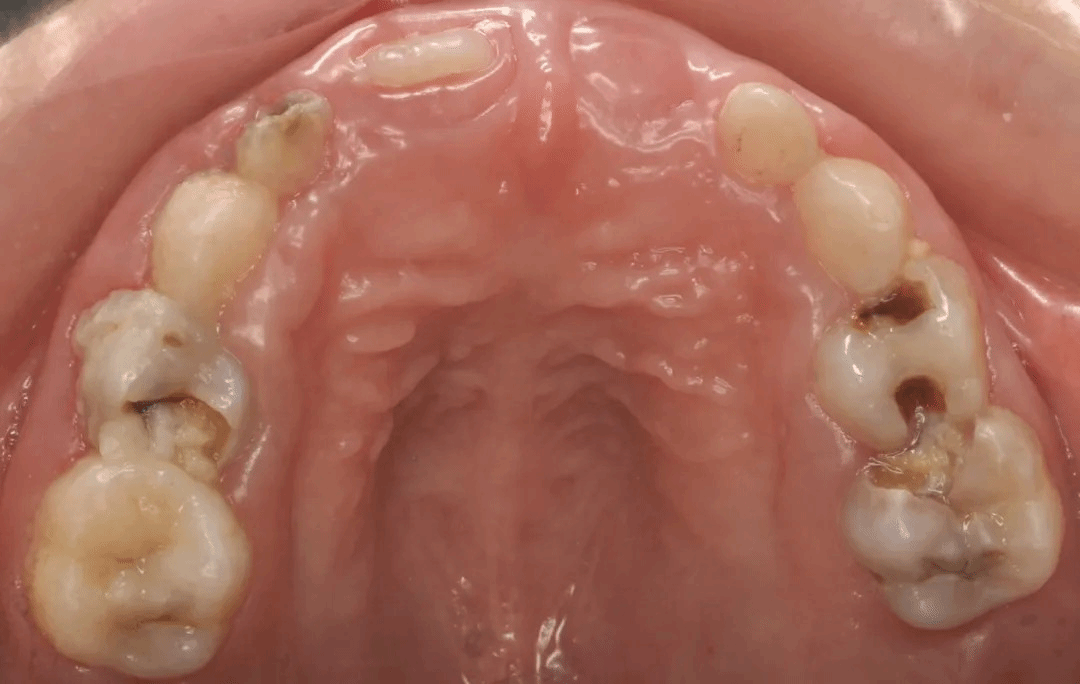

图中可⻅⼝内多⽛蛀⽛,影响进⻝。